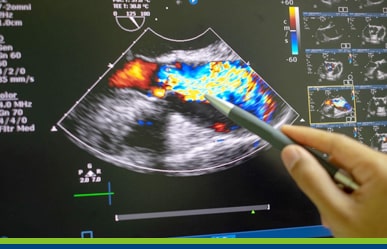

Dentro de mi especialidad me he dedicado al campo de la cardiología clínica y con mayor énfasis a la ultrasonografía, la ecografía cardiaca y vascular, tengo un certificado de NBE, National Board of echocardiography, que reconoce mi capacitación con un estándar de nivel mundial.

Estamos especializados en el diagnóstico y tratamiento de las enfermedades que afectan el corazón y la circulación.

Trabajamos con equipos de última generación.